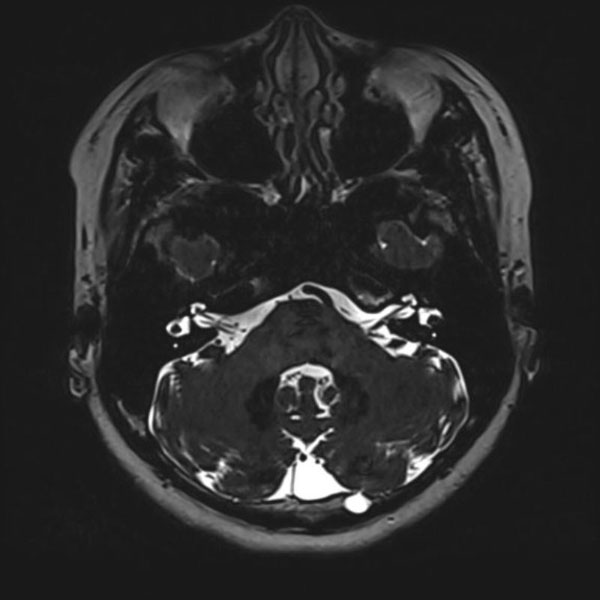

手術前

(MR1)